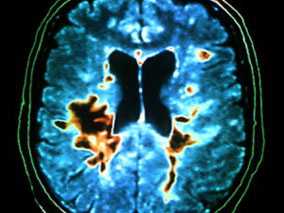

On sait que des lésions cérébrales focales telles que tumeurs, hémorragies ou abcès peuvent provoquer des crises d’épilepsie mais les choses sont moins claires pour les anomalies liées à la sclérose en plaques. Certaines études ont cependant montré une augmentation de la prévalence de l’épilepsie chez les patients souffrant de SEP mais elles étaient de petite taille.

Les mécanismes de l’association entre SEP et épilepsie ne sont pas clairs et font l’objet de plusieurs hypothèses. Certains auteurs ont retrouvé une corrélation entre les crises épileptiques et le nombre de poussées de SEP. D’autres ont observé une inflammation corticale plus sévère et davantage de lésions intracorticales en cas de coexistence des pathologies que dans la SEP isolée. Enfin, des travaux suggèrent qu’une anomalie de l’expression des canaux sodiques neuronaux dans la SEP pourrait jouer un rôle dans l’apparition ultérieure d’une épilepsie.